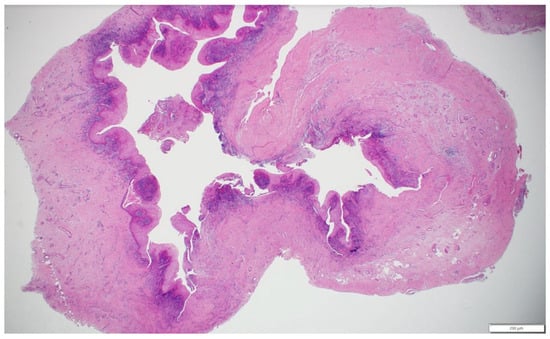

Histopathological analysis (Figure 5) of the excised cystic lesion revealed a cystic structure lined by hyperplastic, non-keratinized odontogenic epithelium exhibiting squamous metaplasia. Several luminal epithelial cells displayed a characteristic “hobnail” appearance, demonstrating epithelial remodeling. The connective tissue wall was thick and highly collagenous, with chronic inflammatory infiltrates predominantly localized adjacent to the epithelial lining. Additionally, the connective tissue contained multiple large blood vessels and several nerve fibers. These findings, along with the clinical and radiographic correlation, confirm that the lesion represents a periapical inflammatory cyst arising from a non-vital tooth.

Figure 5.

Histopathological features of the excised periapical inflammatory cyst, showing non-keratinized odontogenic epithelium with squamous metaplasia and “hobnail” cells, a thick collagenous wall with chronic inflammatory infiltrate, and prominent vasculature and nerve fibers in the connective tissue (hematoxylin and eosin stain, scale bar = 200 μm).